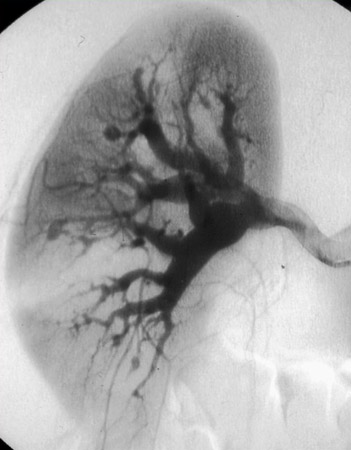

Angiografia renal mostrando aneurismas e microaneurismas

Do acervo do Dr Loic Guillevin